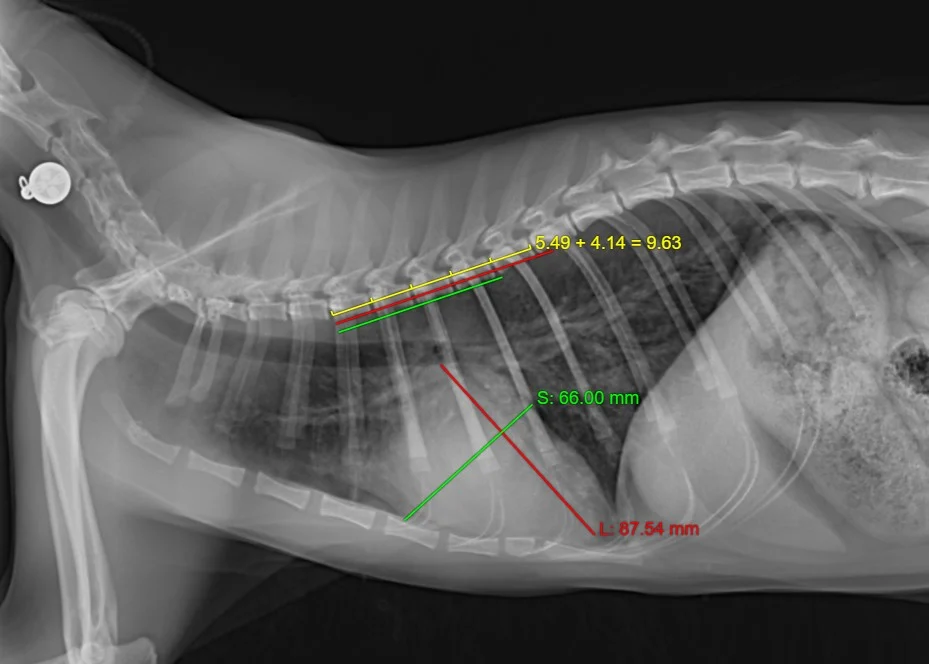

**下方為本院確診之肥大性心肌病貓咪,藉由胸腔X光初步評估心臟有擴大現象並建議飼主再進一步做更詳細的心臟超音波檢查。

胸腔X光可以初步判斷心臟大小有無異狀。心臟長軸L(紅字),垂直L的最寬長度S(綠字),第四至第八胸椎長度M(黃字);(L/M + S/M) 正常狀態<8mm,此貓咪為9.63mm。